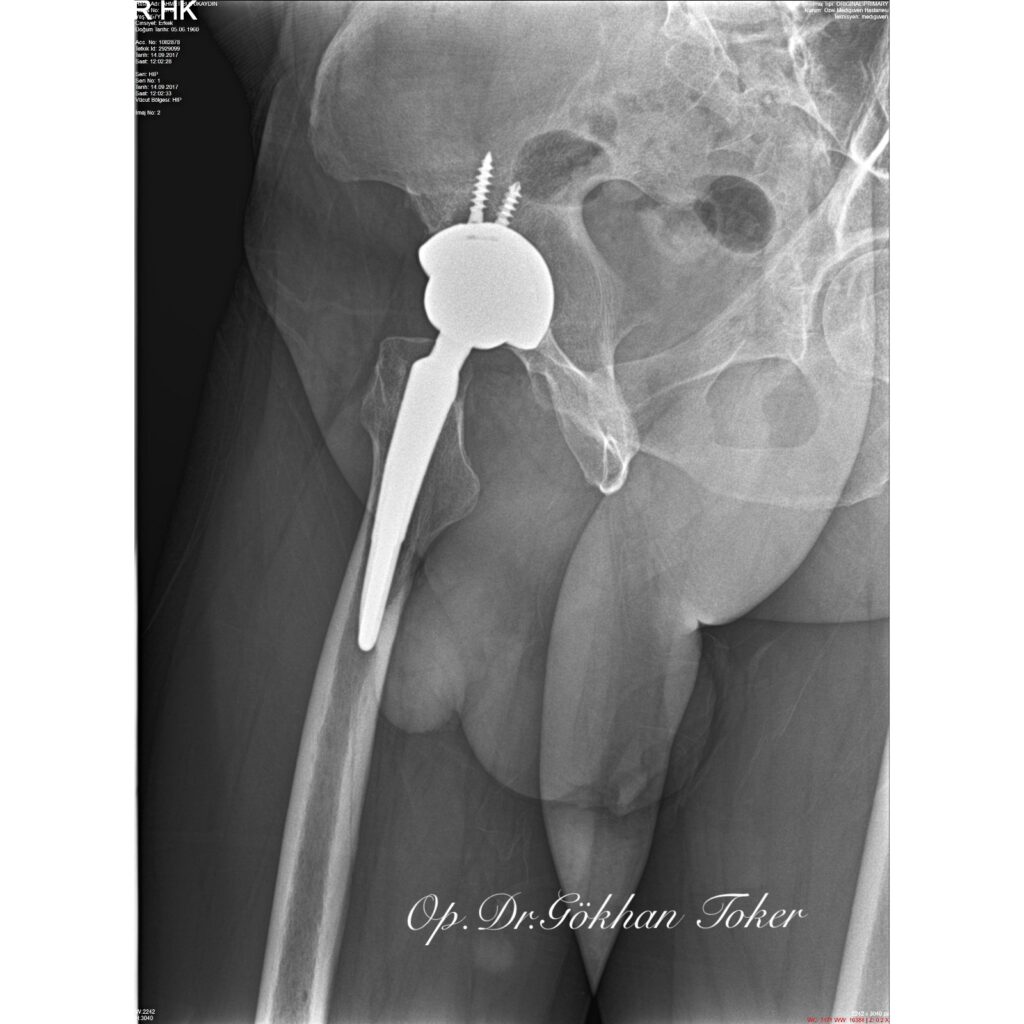

A.C.